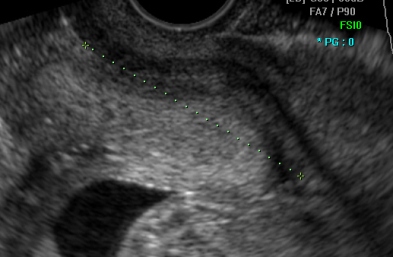

Прегледот на ултразвук во оваа фаза од бременоста најпрво опфаќа мерење на обемот и пречникот на главчето на бебето. Потоа се врши мерење на мозочните структури на бебето, што е особено значајно за откривање на некои тешки вродени малформации на централниот нервен систем. На оваа контрола се мери обемот на стомачето (AC), должината на бутната коска (FL) и должината на коската на надлактицата (хумерус). Овие мерки и нивниот меѓусебен однос даваат значајни информации за растот на бебето. Потоа внимателно се следи континуитетот на рбетниот столб, со цел исклучување на вродените малформации на рбетот (spina bifida). Понатаму може да се прикажат и внатрешните органи, како што е желудникот, мочниот меур и срцето на бебето, кое веќе има јасен четирикоморен пресек со визуелизација на двете предкомори и двете комори. Со доплер се испитува работата на срцето и протокот на крв во папочната врвка. На овој преглед се прикажува и полот на бебето, со доста јасна диференцијација на машките или женските надворешни полови карактеристики.

Како и на другите прегледи, и сега се испитува поставеноста на плацентата и папочната врвка. Се испитува количеството на плодова вода во матката, кое дава значајни информации за состојбата на плодот и неговиот правилен развој. На овој преглед со вагинална сонда се испитува должината на грлото на матката. Овој преглед може да исклучи или да открие инсуфициенција (слабост) на грлото на матката, кое може да попушти под тежината на бебето кое постојано расте. Доколку се утврди скратување, во консултација со гинекологот може да се изврши серклаж. Серклажот претставува гинеколошка процедура на зајакнување на грлото на матката.